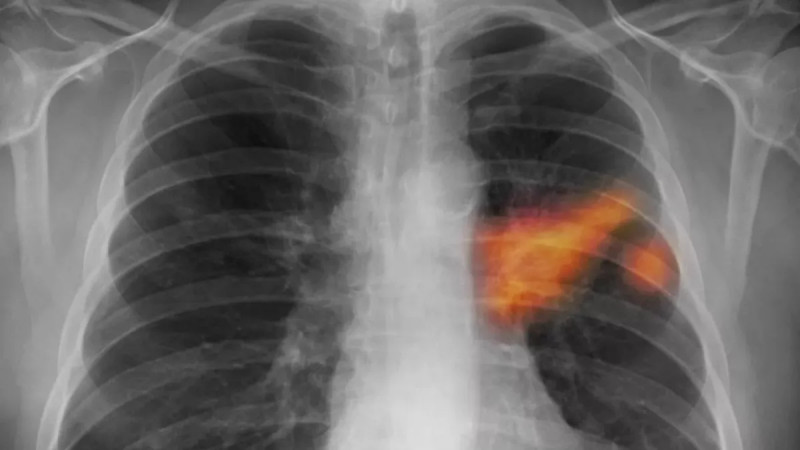

Rok co rok je rakovina plic odhalena u více než 6500 pacientů, přičemž pouze u jednoho z deseti je diagnóza stanovena včasné léčitelném stádiu, přičemž preventivní screening pomůže každému druhému vyšetřenému, avšak polovina oslovených na něj nedochází a praktický lékaři tento vyšetřovací program nabízejí jen polovině svých pacientů. #rakovinaplic #screening #prevencetumoru

Jeden z deseti nádorů plic zachytí lékaři včas, při preventivním vyšetření pět

Každý rok lékaři odhalí rakovinu plic u více než 6500 pacientů, v dobře léčitelném časném stadiu ale jen u desetiny z nich.